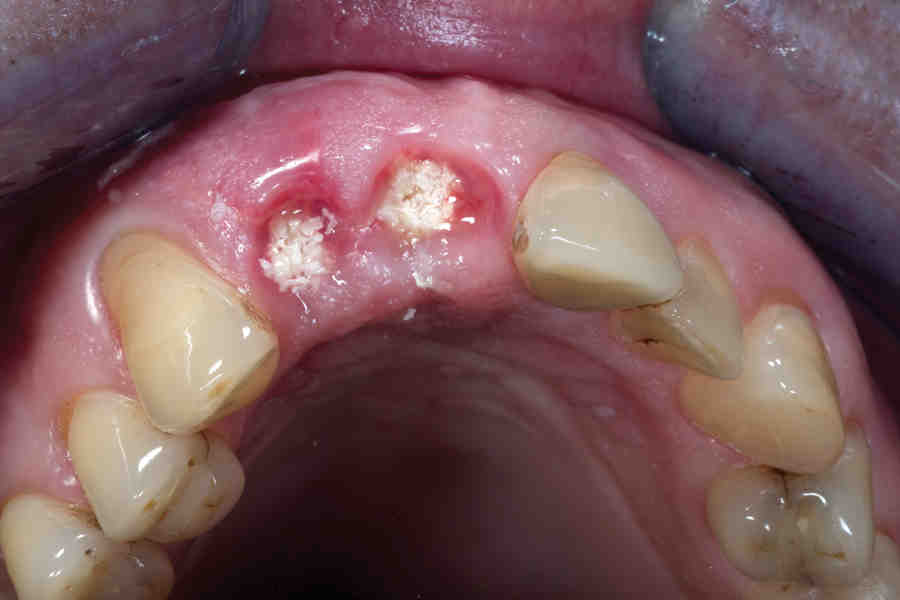

Bone Graft with Immediate Implant Placement Complete Dental Where Does The Bone Graft Come From For Dental Implants Bone grafting is a surgical procedure that aims to create a more solid base for dental implants. A dental bone graft replaces missing or lost bone in your jaw. It involves grafting bone material — either from another. Your surgeon will explain to you which products could be used for your bone grafting procedure. A dental bone graft is a. Where Does The Bone Graft Come From For Dental Implants.